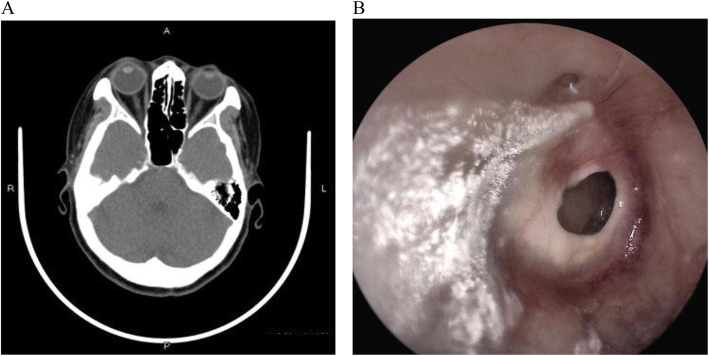

Upon medical checkup, she had a tympanic temperature of 36.5 °C, blood pressure of 129/87 mmHg, pulse rate of 72/min and respiratory rate of 19/min. Computed tomography of mastoid process revealed chronic mastoiditis and tympanic membrane perforation of right side. Aural endoscopy showed that the left external auditory canal unobstructed and the tympanic membrane intact with local calcified plaques; white aerial hyphae can be seen in the right external auditory canal, with large perforation in pars tensa of tympanic membrane, and drum room clean (Fig. 1). Laboratory evaluation revealed leukocyte count of 6810/mm3 with 68.9% neutrophils and 23.7% band forms, total cholesterol 7.2 mmol/L (normal range, 3.1–5.7 mmol/L), high-density lipoprotein 2.02 mmol/L (normal range, 1.09–1.63 mmol/L), lipoprotein(a) 860 mg/L (normal range, 60-300 mg/L).

Fig. 1.

Computed tomography of mastoid process revealed chronic mastoiditis and tympanic membrane perforation of right side (a), and white aerial hyphae can be seen in the right external auditory canal, with large perforation in pars tensa of tympanic membrane in aural endoscopy (b)